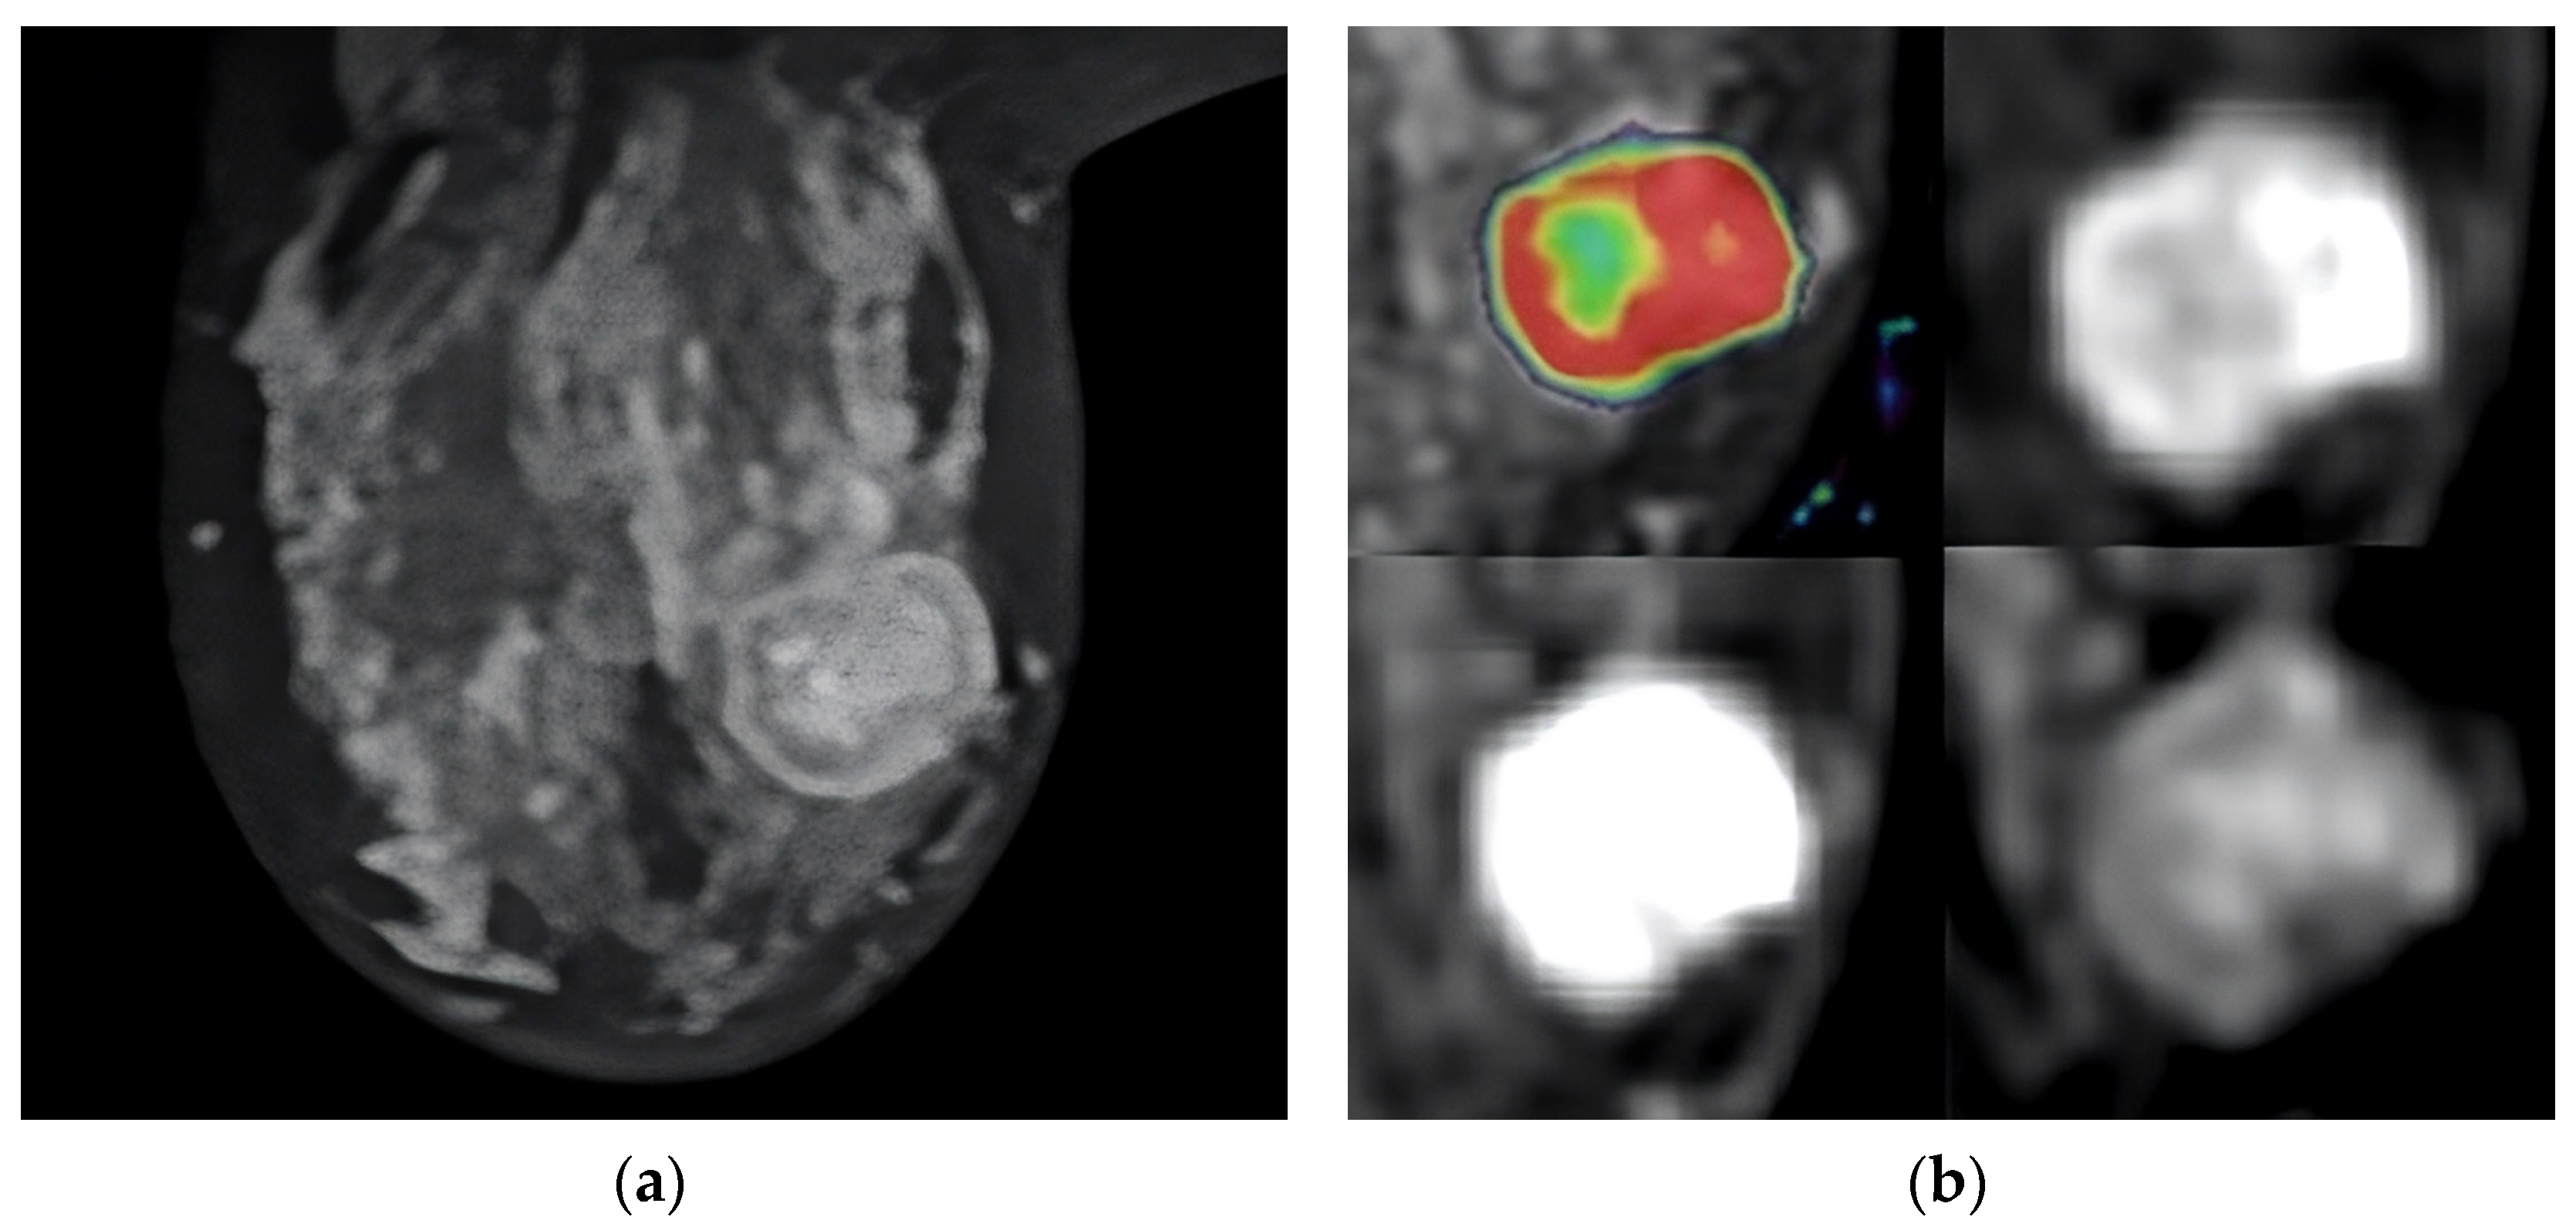

Figure 1.

Ring-enhancing mass in the left breast. A HER-2-positive tumor, Ki-67 index: 45%. (a) Post-contrast image of the tumor demonstrating ring enhancement with a linear enhancing component; (b) overlay of the same image with IAUGC perfusion map, red denotes high perfusion.